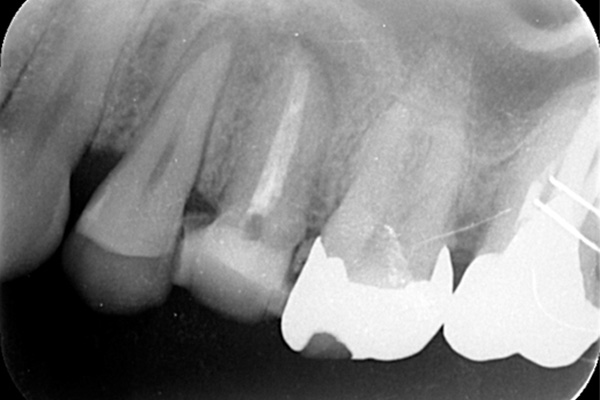

左のレントゲンでは破折したかどうかはわからないが、虫歯になっている部分をとっていくと歯が割れているのがはっきりとわかりました。

歯が割れるケースで多いのが金属の土台(メタルコア)が入っている場合です。特に根の中に長いものが入っていると、歯を割る力が強くかかるため、割れることが多いです。

こちらの写真は違和感があるということでレントゲンを撮ったが異常は見つからなかった。しかし、1ヶ月後にもう一度撮影すると、歯が割れているのがわかりました。また、歯の周りの骨の部分がやや黒くなっているのも分かります。